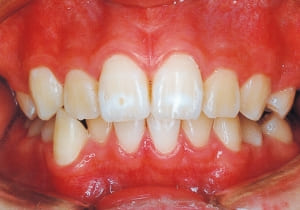

Age at initial visit : 7 y 7 m, male /Protruding upper bite. Open bite. Receding lower jaw. Protruding dual dentition.

1 Initial Visit 2-11-’88

2 After Phase 2 Treatment 6-6-’94

This was a case of significant Protruding upper bite, and early treatment was deemed necessary from a functional perspective.

The Class II condition is pronounced, with a significant overjet of 12.5 mm(3). Although the teeth size are large, crowding is relatively mild. The maxillofacial structure has good depth and a robust bone framework(5). The mandible itself is solid , robust gonial angle, but there is significant anterior-posterior displacement relative to the maxilla(ANB 10.0°). While there is no confirmed history of thumb-sucking or similar habits, the lower lip is already pushing up against the maxillary incisors. The cause of this condition is unknown.